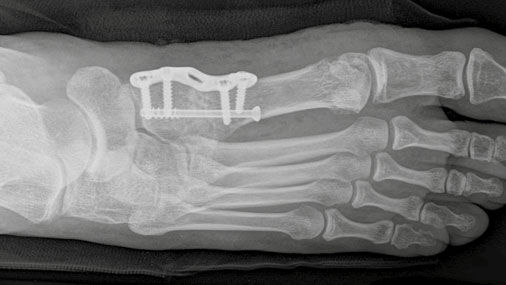

Besteht eine ausgeprägte Instabilität im Bereich der Basis des ersten Mittelfußknochens an seinem gelenkigen Übergang zu den Fußwurzeln (TMT-1-Gelenk), muss zur Korrektur und Stabilisierung dieses Gelenk bei den operativen Maßnahmen mit einbezogen werden, ansonsten droht ein Rezidiv. Diese als Lapidus-Operation bezeichnete Technik beinhaltet die Stellungskorrektur dieses Gelenks und anschließende Fixierung in dieser neuen Position. Durch Anbringen des Plättchens von unten (fußsohlenseitig) wird eine hohe biomechanische Stabilität erreicht. Da die Beweglichkeit dieses Gelenks nur sehr gering ist fällt eine Versteifung funktionell fast nicht ins Gewicht.

Operation nach Lapidus, fußsohlenseitige (plantare) Plattenfixierung.

Bildquelle: Arthrex GmbH

Hallux valgus nach Lapidus-Operation im Röntgenbild